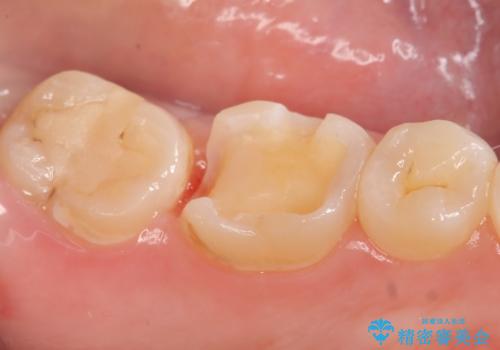

- 冷たいものを飲むと、左下奥歯がしみると来院された方の症例です。

検査の結果左下6が虫歯になっていたため、セラミックインレーによる修復を行いました。